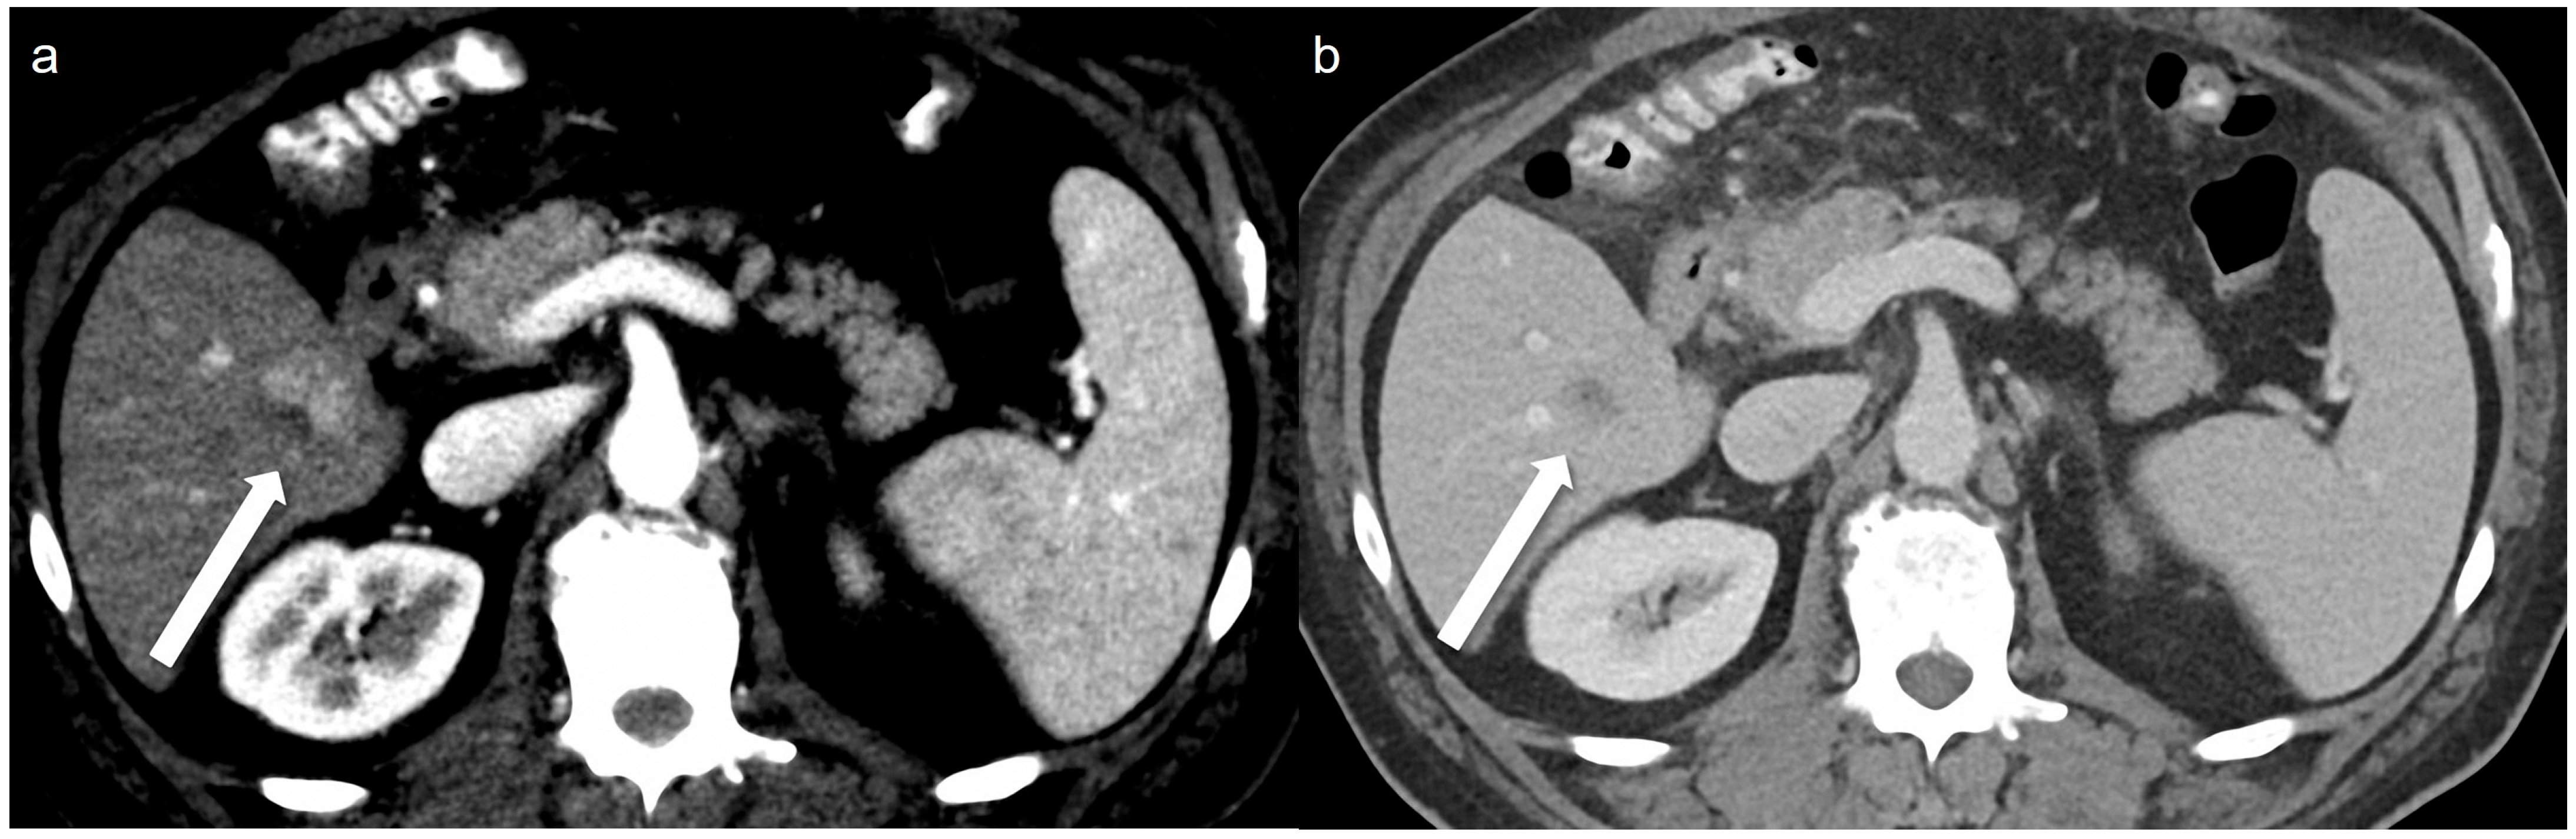

Figure 4.

A 51-year-old man with 2 cm hepatocellular carcinoma (HCC). The low-concentration contrast medium (270 mg I/mL) monoenergetic 40 keV image (a) shows arterial enhancement (arrow), and the portal venous phase (b) shows washout (arrow).